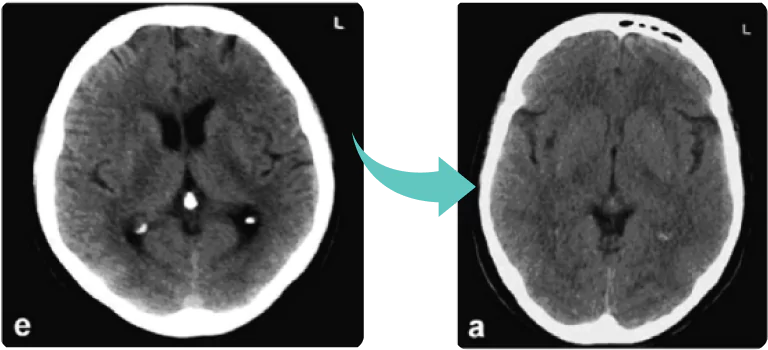

In another clinical study conducted at the University of Pittsburgh, Alzheimer’s patients received 60 mg of Moringa extract for four weeks.

Advanced imaging showed something remarkable:

a reduction in calcification of the pineal gland, which typically builds up over years due to fluoride and toxin exposure.